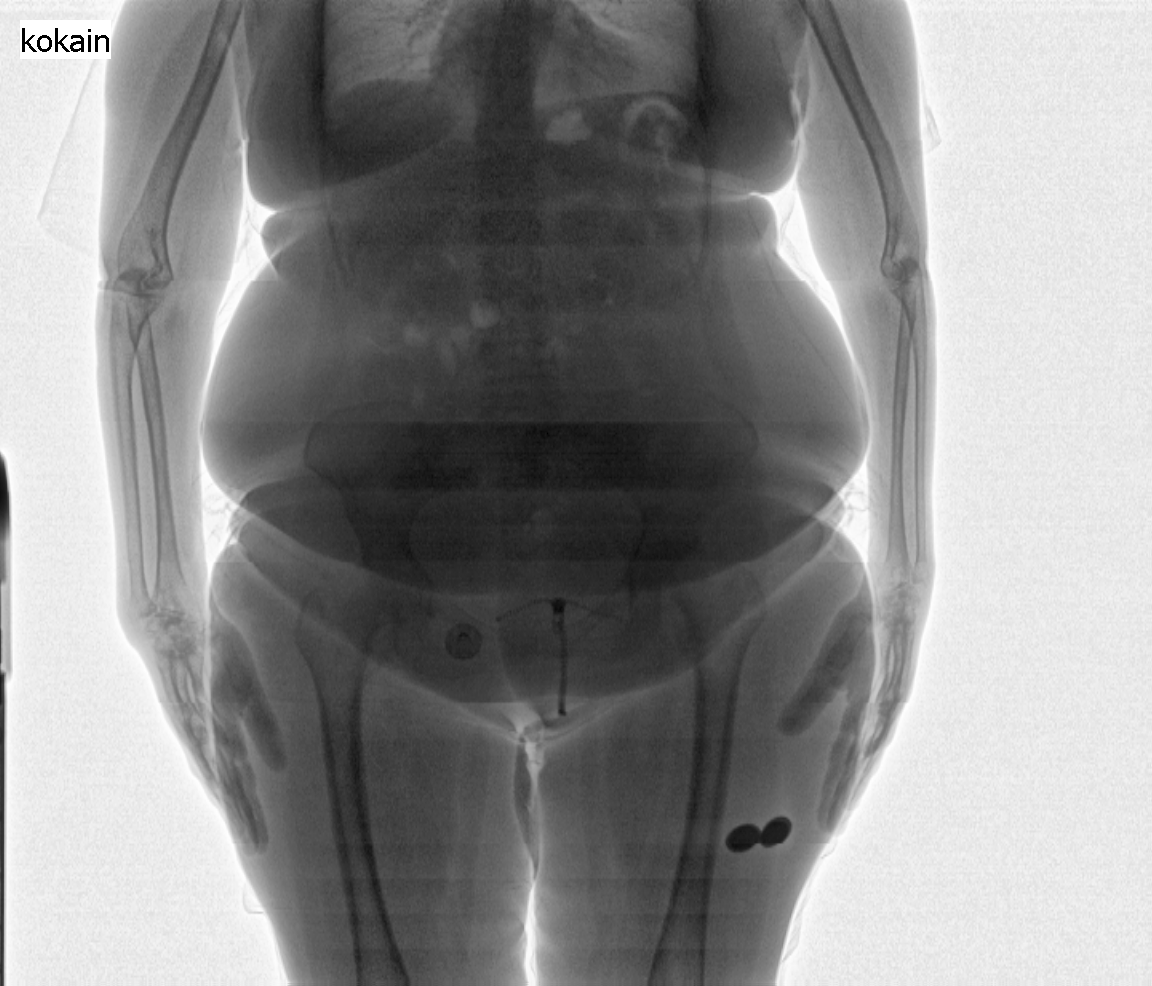

Selve scanningen foregår ved, at personen bliver placeret, fuldt påklædt, på en platform i bilen, som på få sekunder kører forbi scanneren. Scanneren tager to røntgenbilleder: et af hele kroppen og et kun af torso. Billederne overføres straks til scanneroperatøren, der sidder i bilens operatørrum. Hvis operatøren ser, at der er gemt uidentificeret indhold i kroppen, bliver den mistænkte person overgivet til politiet, der vil stå for den videre håndtering.

Scanningsbillede 1 - person med 91 kugler kokain med samlet vægt på ca. 1 kg.